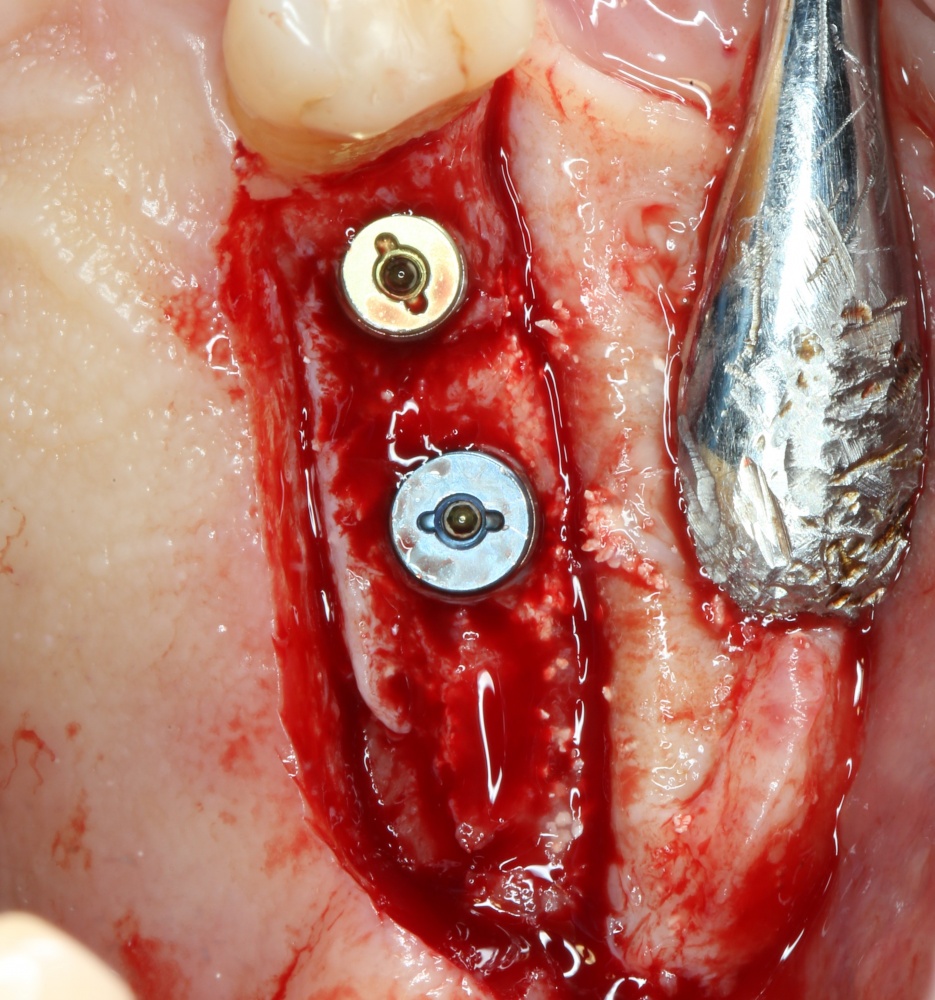

Через 3 месяца — вторая операция — установка имплантата в сформированный объем костной ткани:

Как видите. восстанавливается всё очень легко, никаких дефектов не остаётся, но при этом мы получаем важное преимущество: достаточную свободу движений при формировании субантральной полости и хороший визуальный контроль за состоянием слизистой оболочки. Никакая нажопная оптика или суперпупермикроскоп, к сожалению, не обеспечат подобный контроль при закрытом синуслифтинге. Да, операция получается травматичнее и масштабнее, чем «закрытый» синуслифтинг, но несёт в себе гораздо меньше рисков.